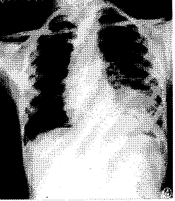

肺包蟲囊腫作為含液囊腫,立位透視吸氣時膈肌下降,頭、足徑稍增加,呼氣膈肌上升時,則橫徑稍長,上下稍短(“包蟲呼吸征”)。較大囊腫把肺紋理撐開,周圍的肺紋理呈條索狀包繞著囊腫的向肺門側(“抱球征”)。大囊腫可呈分葉狀或多環狀。下肺野的囊腫“坐在”膈肌上,使膈肌位置下降,甚至凹陷,有時須行人工氣腹以明確是否為胸內囊腫。上肺的大囊腫常把縱隔推向對側,在下葉的縱隔受影響少,而右肝頂部的巨大囊腫則明顯使心臟向左移位,這個特點有助於鑑別診斷。少數病例有肺不張及胸膜炎。

如囊腫小支氣管被侵犯穿透,少量氣體進入內外囊之間,則出現一些特殊X線征:①少量氣體進入內外囊之間,立位X 線攝片氣體上升至囊腫上部,局部有一弧形透明帶(“新月征”)。②如氣體進一步進入內囊,出現液平面,其上方見有代表內囊及外囊的2 個弧形陰影(“雙弓征”)。③當內囊破裂萎陷,皺縮的內囊浮於液面上,囊內液面上能見到不規則影(“水上浮蓮征”)。

如囊腫破裂,內容物咳淨,又未發生感染,胸片上表現為薄壁邊緣光滑的含氣囊腫。以後囊腔逐漸縮小,僅留有一些纖維化陰影。如囊腫破後發生感染,則囊壁增厚,周圍有慢性炎症出現的可見肺浸潤片狀影。如破入胸腔,有胸腔積液或液氣胸。